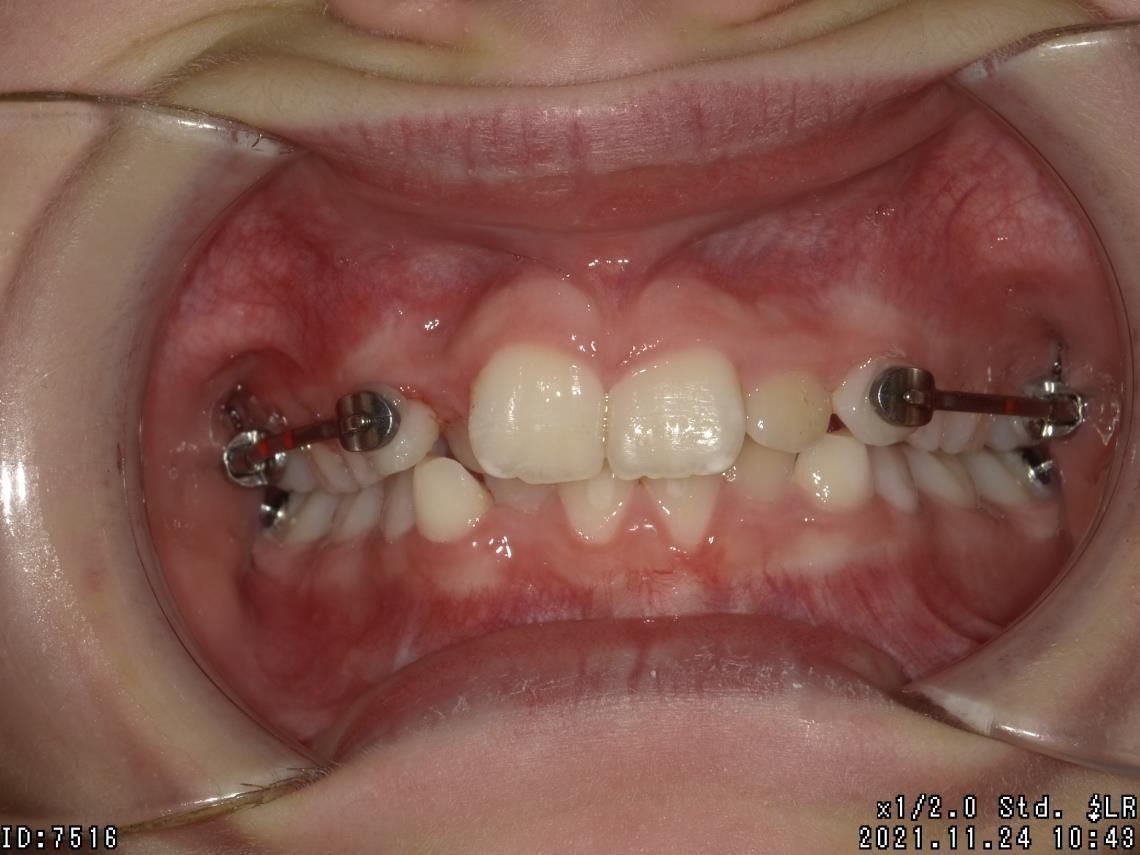

LES BAGUES

Cet appareil dentaire fixe est composé de brackets ou bagues, sortes de petits boutons en métal, en plastique ou en céramique, collés sur les dents et reliés par un fil. Il permet de déplacer les dents du patient dans la direction optimale, de les réaligner au fur et à mesure, de traiter des cas complexes de manque de place et des dents retenues ou dystopiques. Le traitement est moins tributaire de la coopération du patient.